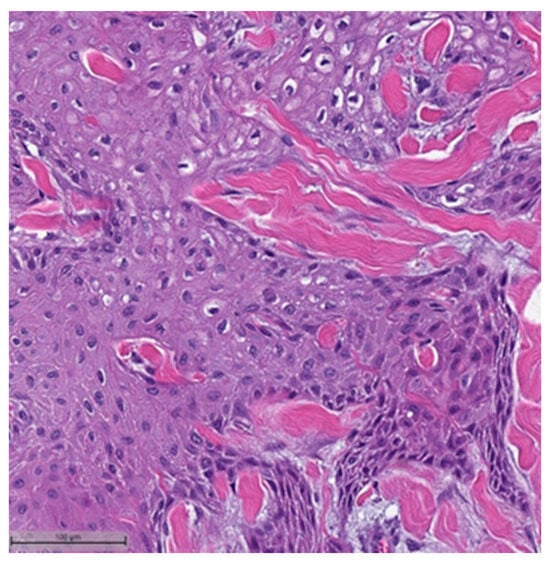

This system is primarily based on the specific metaplastic elements present within the tumors, while also highlighting the potential overlap that can exist between various histological subtypes [6]. Consequently, numerous cases diagnosed as MpBCs, are accompanied by a detailed description of the histological component or a combination of different component types and/or differentiations. The following figures illustrates a few examples: spindle cell carcinoma component with pleomorphic features (Figure 4), metaplastic breast carcinoma with chondroid differentiation (Figure 5), metaplastic breast carcinoma with a matrix-producing component (Figure 6), metaplastic breast carcinoma with osseous differentiation (Figure 7), and extensive trabeculae bone and hematopoietic tissue (Figure 8).

Figure 7.

Metaplastic breast carcinoma with osseous differentiation (H&E, 20×).

Figure 8.

Same case in Figure 7: showing extensive obvious bone trabeculae and hematopoietic tissue (H&E, 20×).